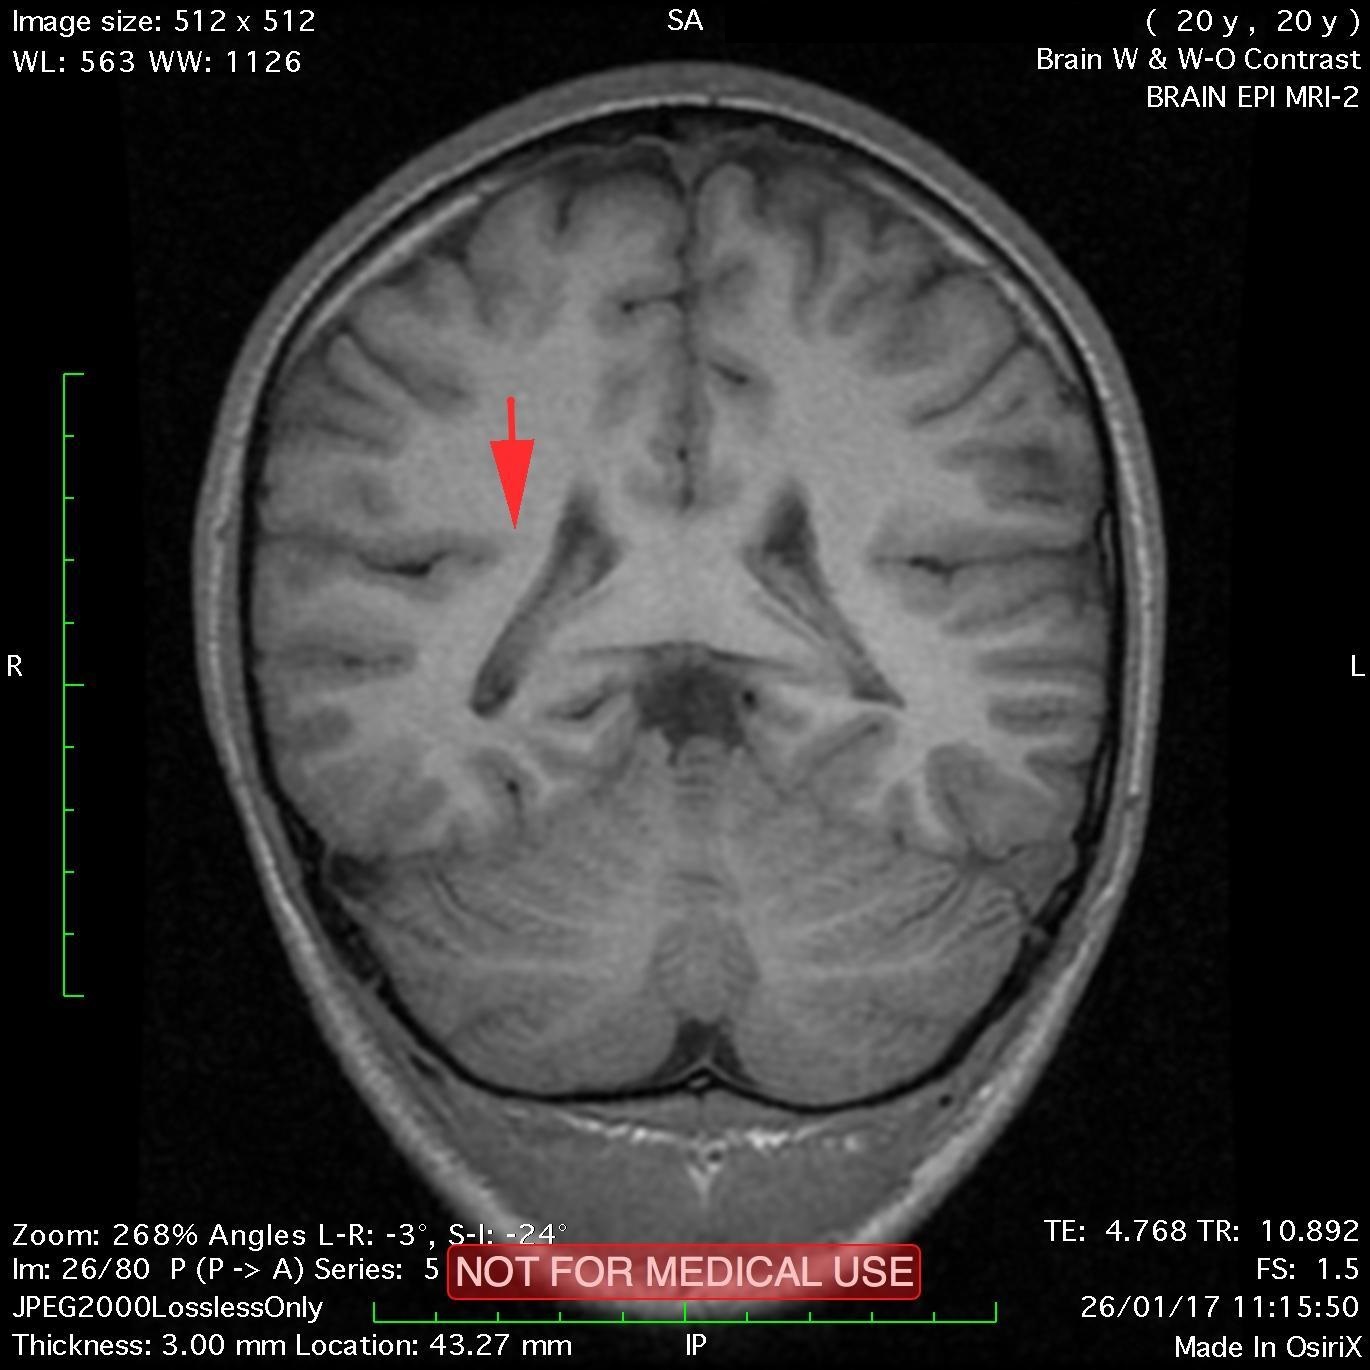

This recent MRI exam WITHOUT Contrast in IHC, revealed a subtle congenital malformation of cortical development within right parietal lobe.

A subtle linear band intensity extending between deep posterosuperior aspect of right Sylvian fissure and posterior aspect of corpus of right lateral ventricle (isointense with gray matter on all sequences). These MRI findings strongly suggest "Type II (Taylor type) focal cortical dysplasia (transmantle cortical dysplasia)" or "transmantle gray matter heterotopia". Virtually, they may be representing two different names for the same entity.

Secondary hippocampal sclerosis is identified, bilaterally (secondary to long-term intractable epilepsy).